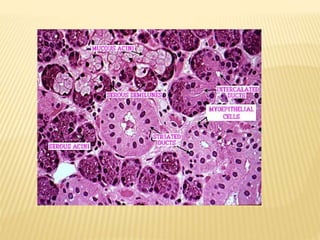

STRUCTURE OF TERMINALSECRETORYUNITS  The basic functional unit of a salivary gland is the terminal secretory unit called ACINI.  Acinar cells of Salivary Glands are classified as :- SEROUS ACINI MUCOUS ACINI MIXED ACINI PRODUCE THIN PRODUCE MORE BOTH SEROUS & WATERY SECRETION VISCOUS MUCUS MUCOUS ACINI; SECRETION MUCOUS HAVE CAP OF SEROUS ACINI , KNOWN AS SEROUS DEMIUNES

SEROUS ACINI Serousacini are protein secreting cells  Structure  Pyramidal with broad base on basement membrane  Apex faces lumen  Spherical nucleus placed at basal region, occasionally binucleated  (Lumen is not usually visible at light microscope level)

MUCOUS ACINI  Mucousacini are mucin secreting cells  Structure  Tubular configuration  Round profiles surrounding central lumen of larger size than serous end pieces with  Apex of cell appears empty  Have serous associated them in form of demilunes.

MYOEPITHELIAL CELLS  Contractilecells associated with secretory end pieces and intercalated ducts  Stellate shaped with flattened nuclei, scanty cytoplasm, long branching processes  Intercalated ducts have fusiform shape and elongated processes  These cells lies between basal lamina and joined to each other by desmosomes

INTERCALATED DUCTS  Primarysaliva produced by secretory end pieces passes first through it  First cell of duct is adjacent to end pieces, lumen is continuous with lumen of intercalated duct  Lined by simple cuboidal epithelium, myoepithelial cell bodies  Diameter of duct is smaller than end pieces but their lumen is larger than end pieces

 Constitute largestportion of duct system  Located within lobules of duct STRIATED DUCTS

 Overall diameterof duct is greater than secretory end pieces  Lumen larger than those of secretory end pieces and of primary intercalated ducts  Function  Modification saliva secretion Reabsorption and of electrolytes